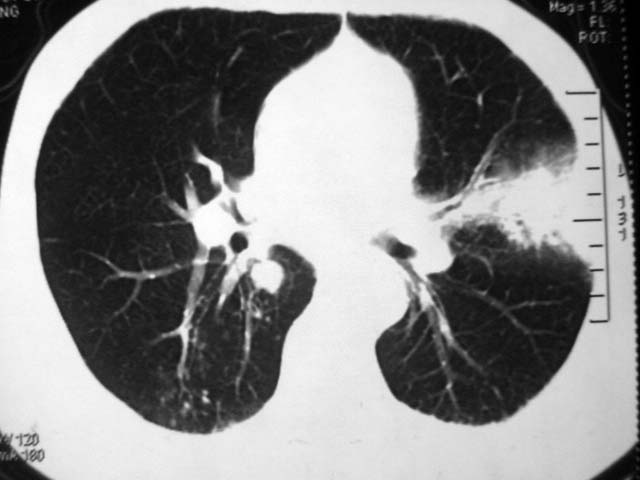

男,52岁,发热2月,糖尿病史。

抗结核治疗irpz方案,血糖未治疗,空腹15.9左右。症状无好转,左胸痛。

复查ct

2、双肺见多发片状及结节状高密度影,大多数病灶中心均见“空泡征”。

3、纵隔内淋巴结肿大。

结果:两肺继发性肺结核并曲霉菌感染。